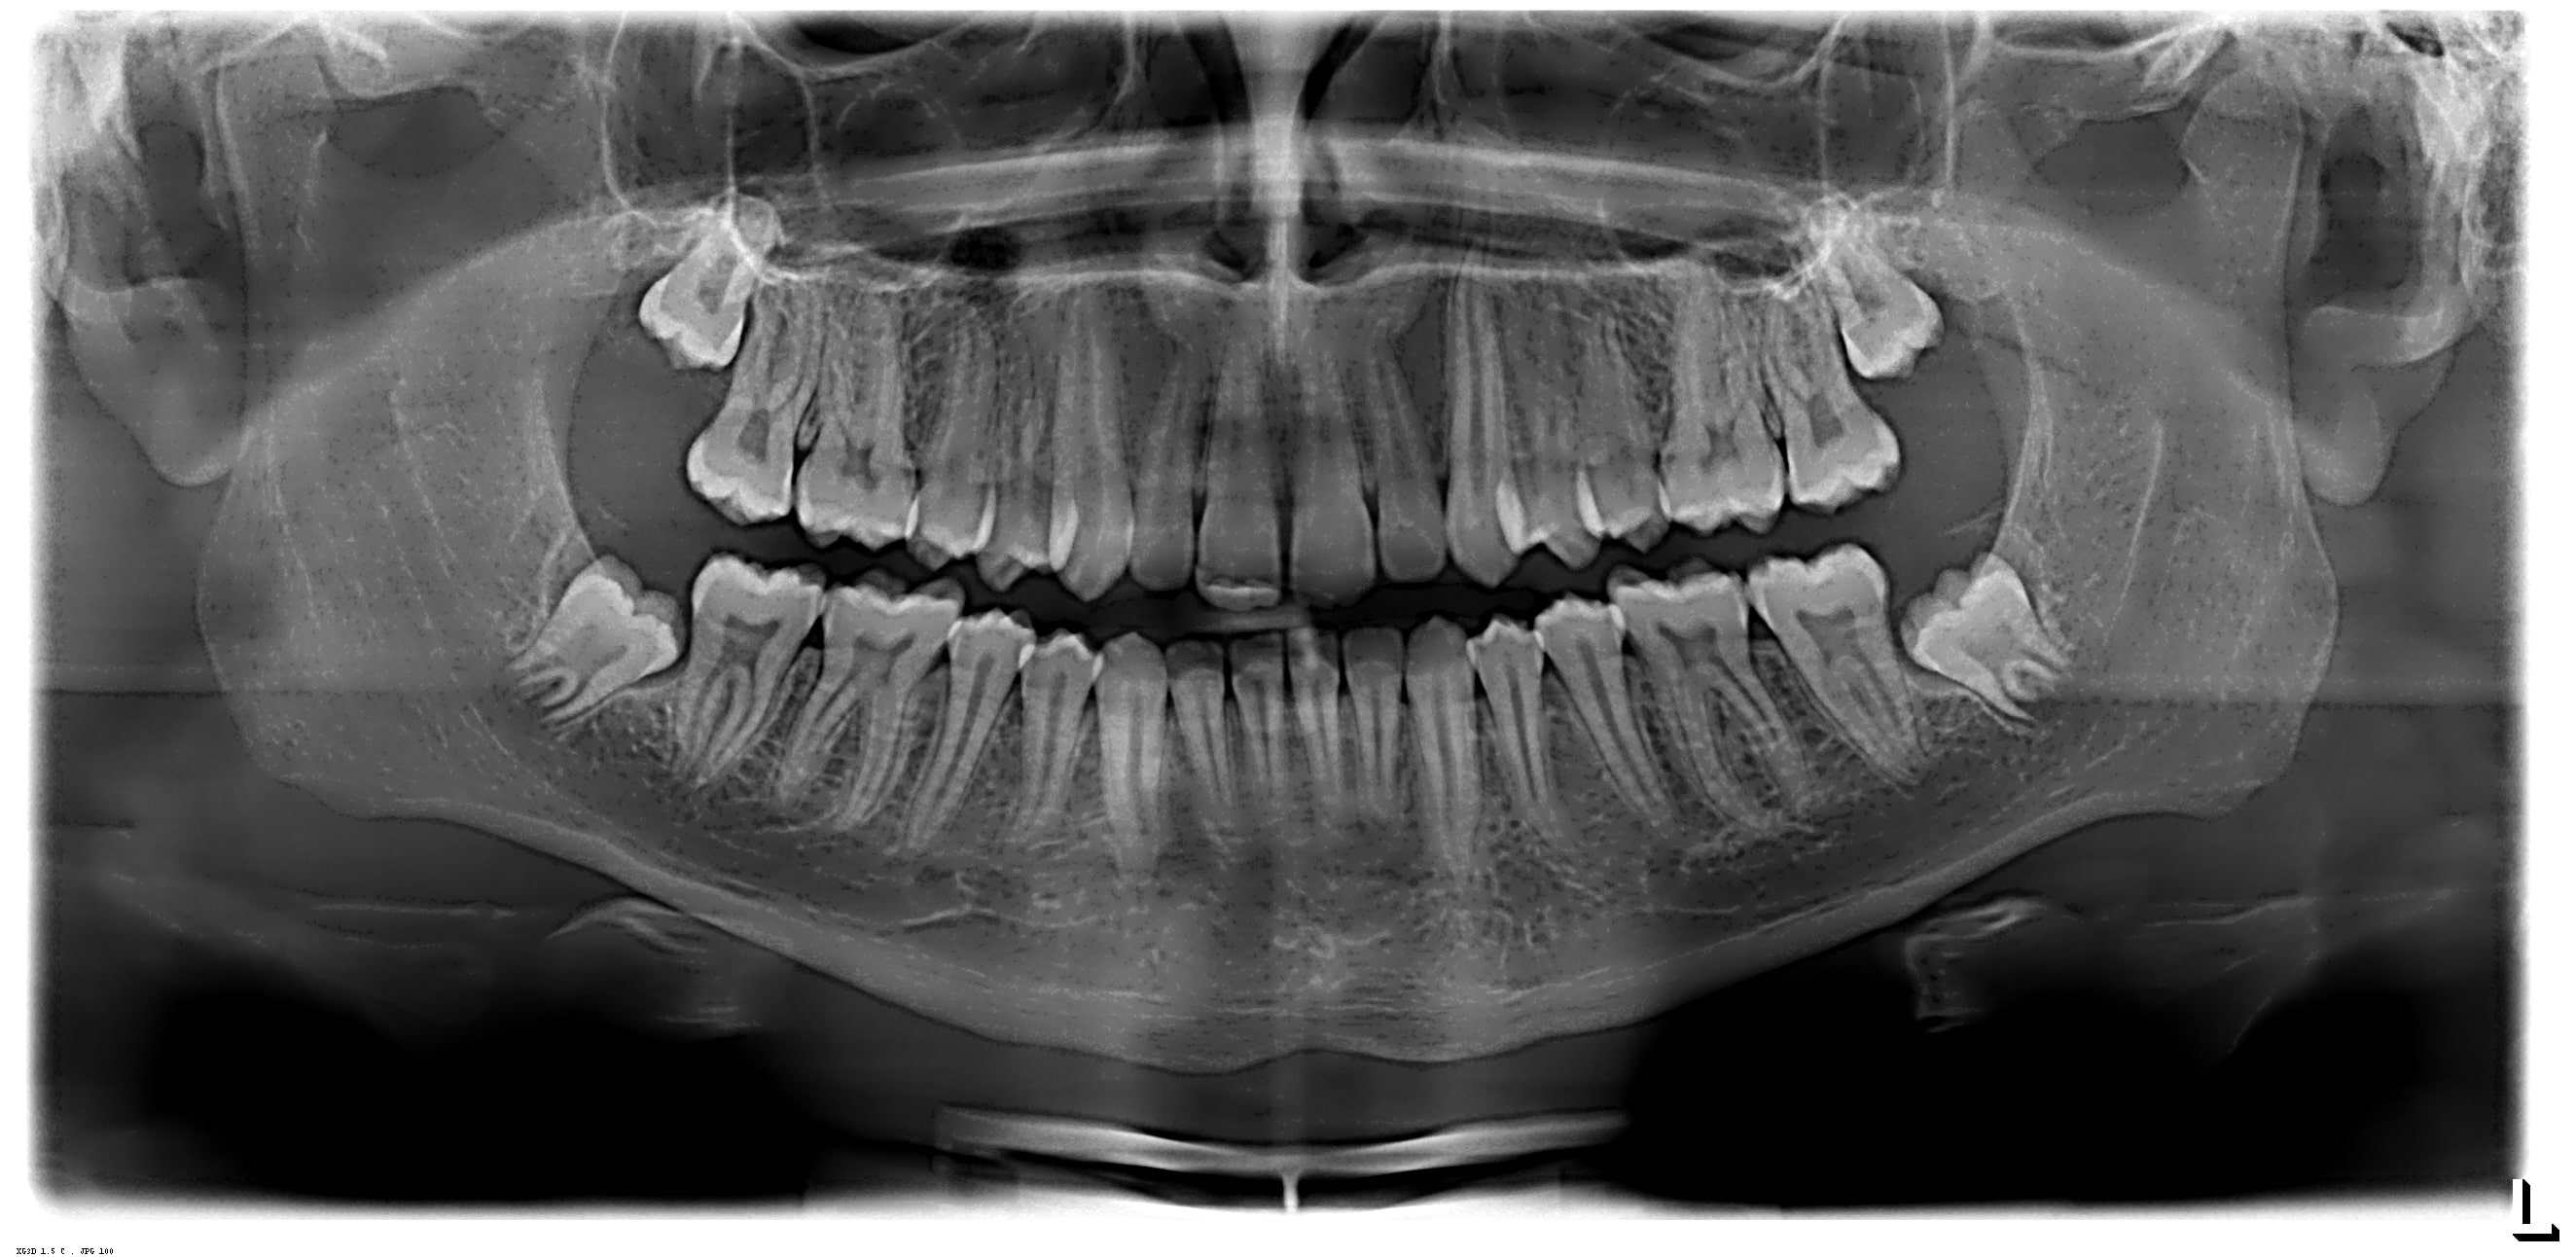

Raio X Panorâmico